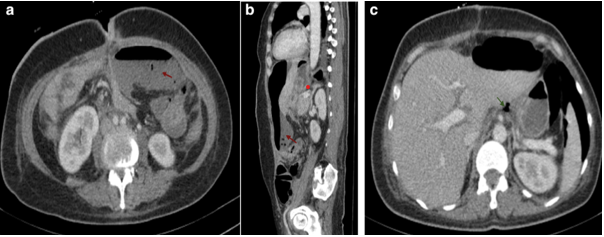

Kehr's Sign in Postoperative Digestive Surgery: A Radiological Red Flag for Pneumoperitoneum

Bouanane Rania, Retal Hamza, El Aouadi Salma, Taibi Ouiam, Siham El Haddad, Nazik Allali and Latifa ChatChatgpt login